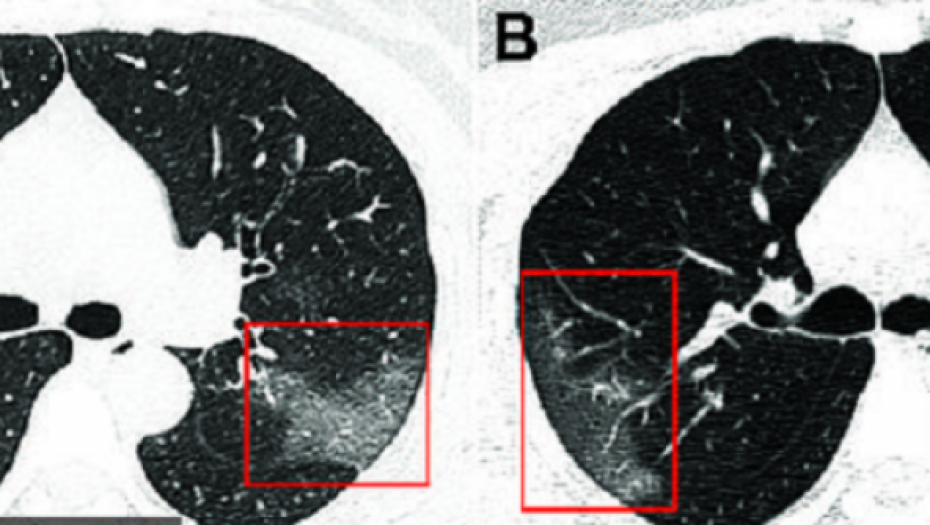

Na snimcima su lekari uočili bele senke, poput takozvanog mlečnog stakla, što ih je upozorilo na to da su pluća delimično ispunjena tečnošću.

Lekari kažu da je u početku vrlo lako pomešati koronavirus sa upalom pluća. Skener je pokazao da se kroz tri dana stanje pacijenta pogoršava, što je bio slučaj i sa SARS-om i MERS-om, virusima koji su takođe harali Kinom početkom 21. veka. Na narednom skeneru su lekari uočili da su bele fleke izraženije što je isključilo upalu pluća i pomoglo im da shvate da treba na drugačiji način da se bore sa ovom bolešću jer obični antibiotici neće pomoći.